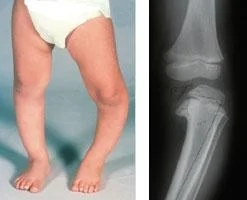

Pediatric Orthopedic

- Pediatric orthopedics